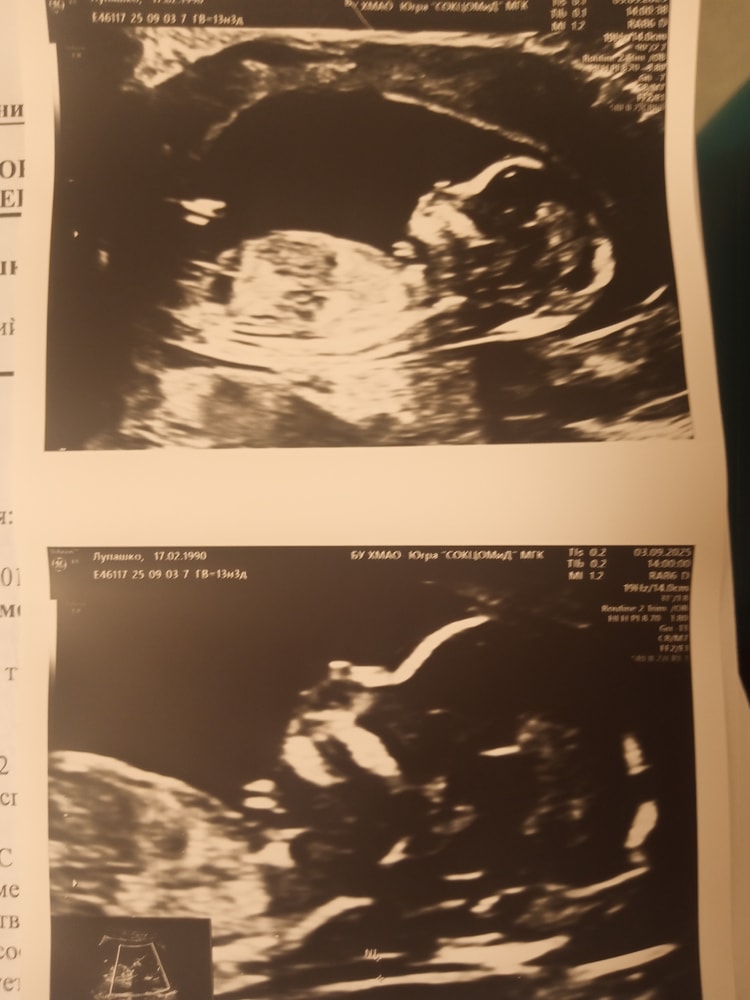

Экспертное узи

03.09.2025

Узи на 5 неделе 3 дня. (4-5недель) эмбриональный Отслойка хориона на 7 неделе 3 дня